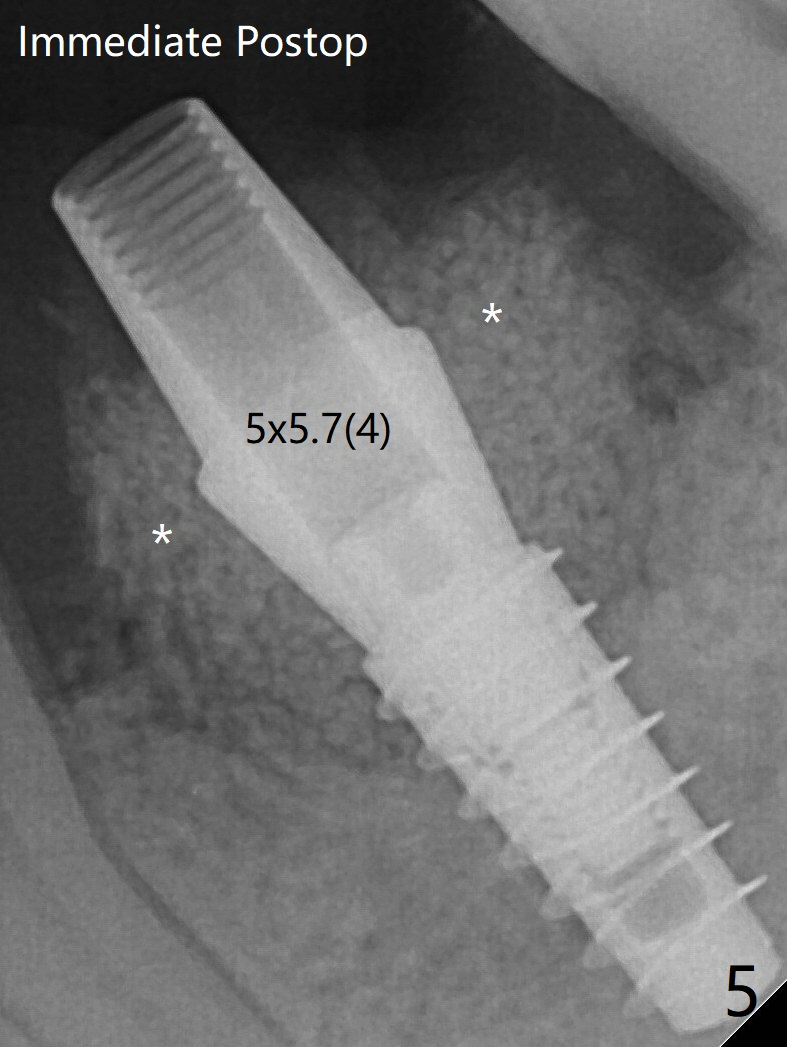

After fine turning, the abutment is fully seated; final round of bone graft (sticky bone) is placed mesiodistally (Fig.5 *) and buccolingually (Fig.6,7).  It appears that there is tight fit between IBS implant and abutment.  It is hoped that the excess bone graft with PRF is able to cover the coronal portion of the implant.  If not, socket preservation should be done in this situation in the future.  In fact there is bone coverage coronally 5 months postop (Fig.8).